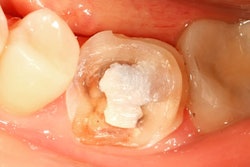

To that end, the researchers conducted a randomized clinical trial to evaluate the results of restorations of noncarious cervical lesions with two newer flowable composites: Filtek Supreme XTE Flow (3M ESPE) with a slightly modified conventional matrix composition, and N'Durance Dimer Flow (Septodont) with novel matrix technology.

The study included 50 patients from one private dental practice in Germany. They each underwent restoration of noncarious cervical lesions in two premolars with the two composites performed by one experienced general dentist. Composite treatment assignment of each tooth was randomized. Clearfil Protect Bond (Kuraray) in self-etch mode was used as the adhesive.

At baseline, they judged all restorations clinically acceptable, which was defined as having a clinically acceptable score (1 through 3) in the FDI criterion of fracture of material and retention. At 30 months, the researchers found 96% of the restorations to be clinically successful, but the percentage dropped to 84.2% of the Filtek and 94.7% of the N'Durance restorations at 60 months.

The researchers found marginal adaptation and fracture of material and retention to be similar in both groups at all time points. However, at 60 months, they found six Filtek and two N'Durance restorations clinically unacceptable for fracture of material and retention, and three Filtek and two N'Durance clinically unacceptable for marginal adaptation.